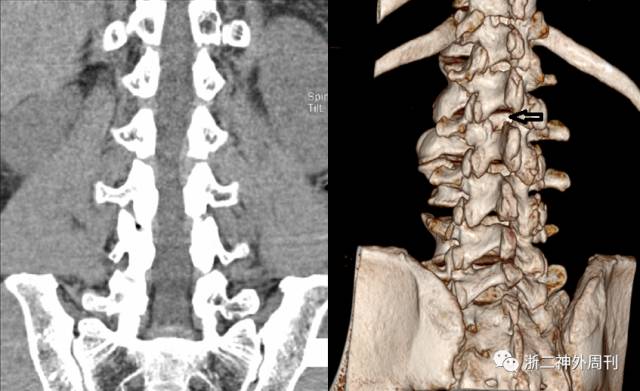

图2. 腰椎CT平扫,腰2椎体水平椎管内占位,病灶病灶类圆形,边界清晰,位于椎管左侧膜外间隙,病灶平均密度约15-20Hu。囊壁菲薄均匀。

图6. 术后10个月腰椎CT平扫,VRT显示L2左侧上椎板骨质稍缺损。(如箭头所示)